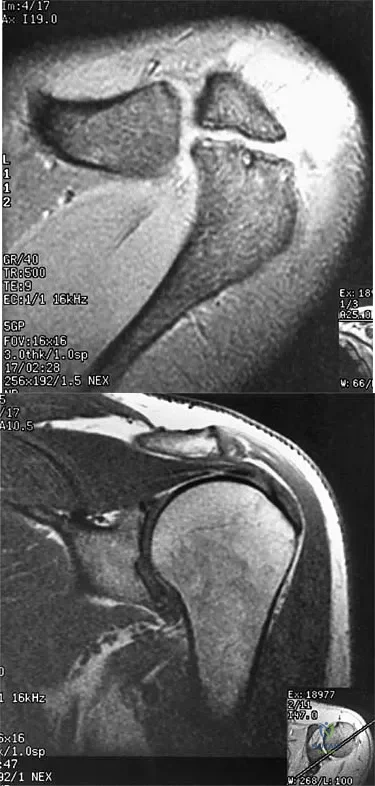

A 47-year-old male tennis player has pain in his nondominant shoulder that has failed to respond to 4 months of nonsurgical management. Examination reveals acromial tenderness and pain at the supraspinatus tendon insertion. He has a positive impingement sign, pain on forward elevation, and minimal cuff weakness. The MRI scans are shown in Figures 30a and 30b. To completely resolve his symptoms, treatment should consist of

Explanation